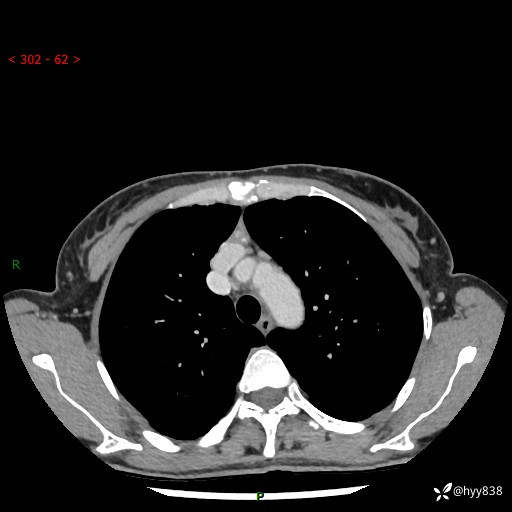

增强动脉期+静脉期